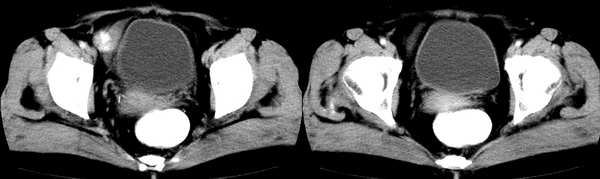

女,59岁,憋气、下腹不适一个月。胸透:双侧大量胸腔积液,反复抽胸水化验为漏出液。彩超示:盆腔占位

右侧卵巢区囊实性占位性病变,内见高密度及囊性脂肪密度,实性部分强化明显,囊性部分未见强化,结合病史多考虑:右侧卵巢恶性畸胎瘤。

右侧卵巢区囊实性占位性病变,内见高密度及囊性脂肪密度。考虑:右侧卵巢恶性畸胎瘤。

膀胱右前方类圆形软组织占位,边界光整,增强后明显强化,与口服造影剂密度相当,随后密度减低,强化均匀,考虑盆腔右侧血管源性占位。

麦格综合症(卵巢纤维瘤并胸水)。

支持麦格综合症(卵巢纤维瘤并胸水)。生殖器官恶性肿瘤待排